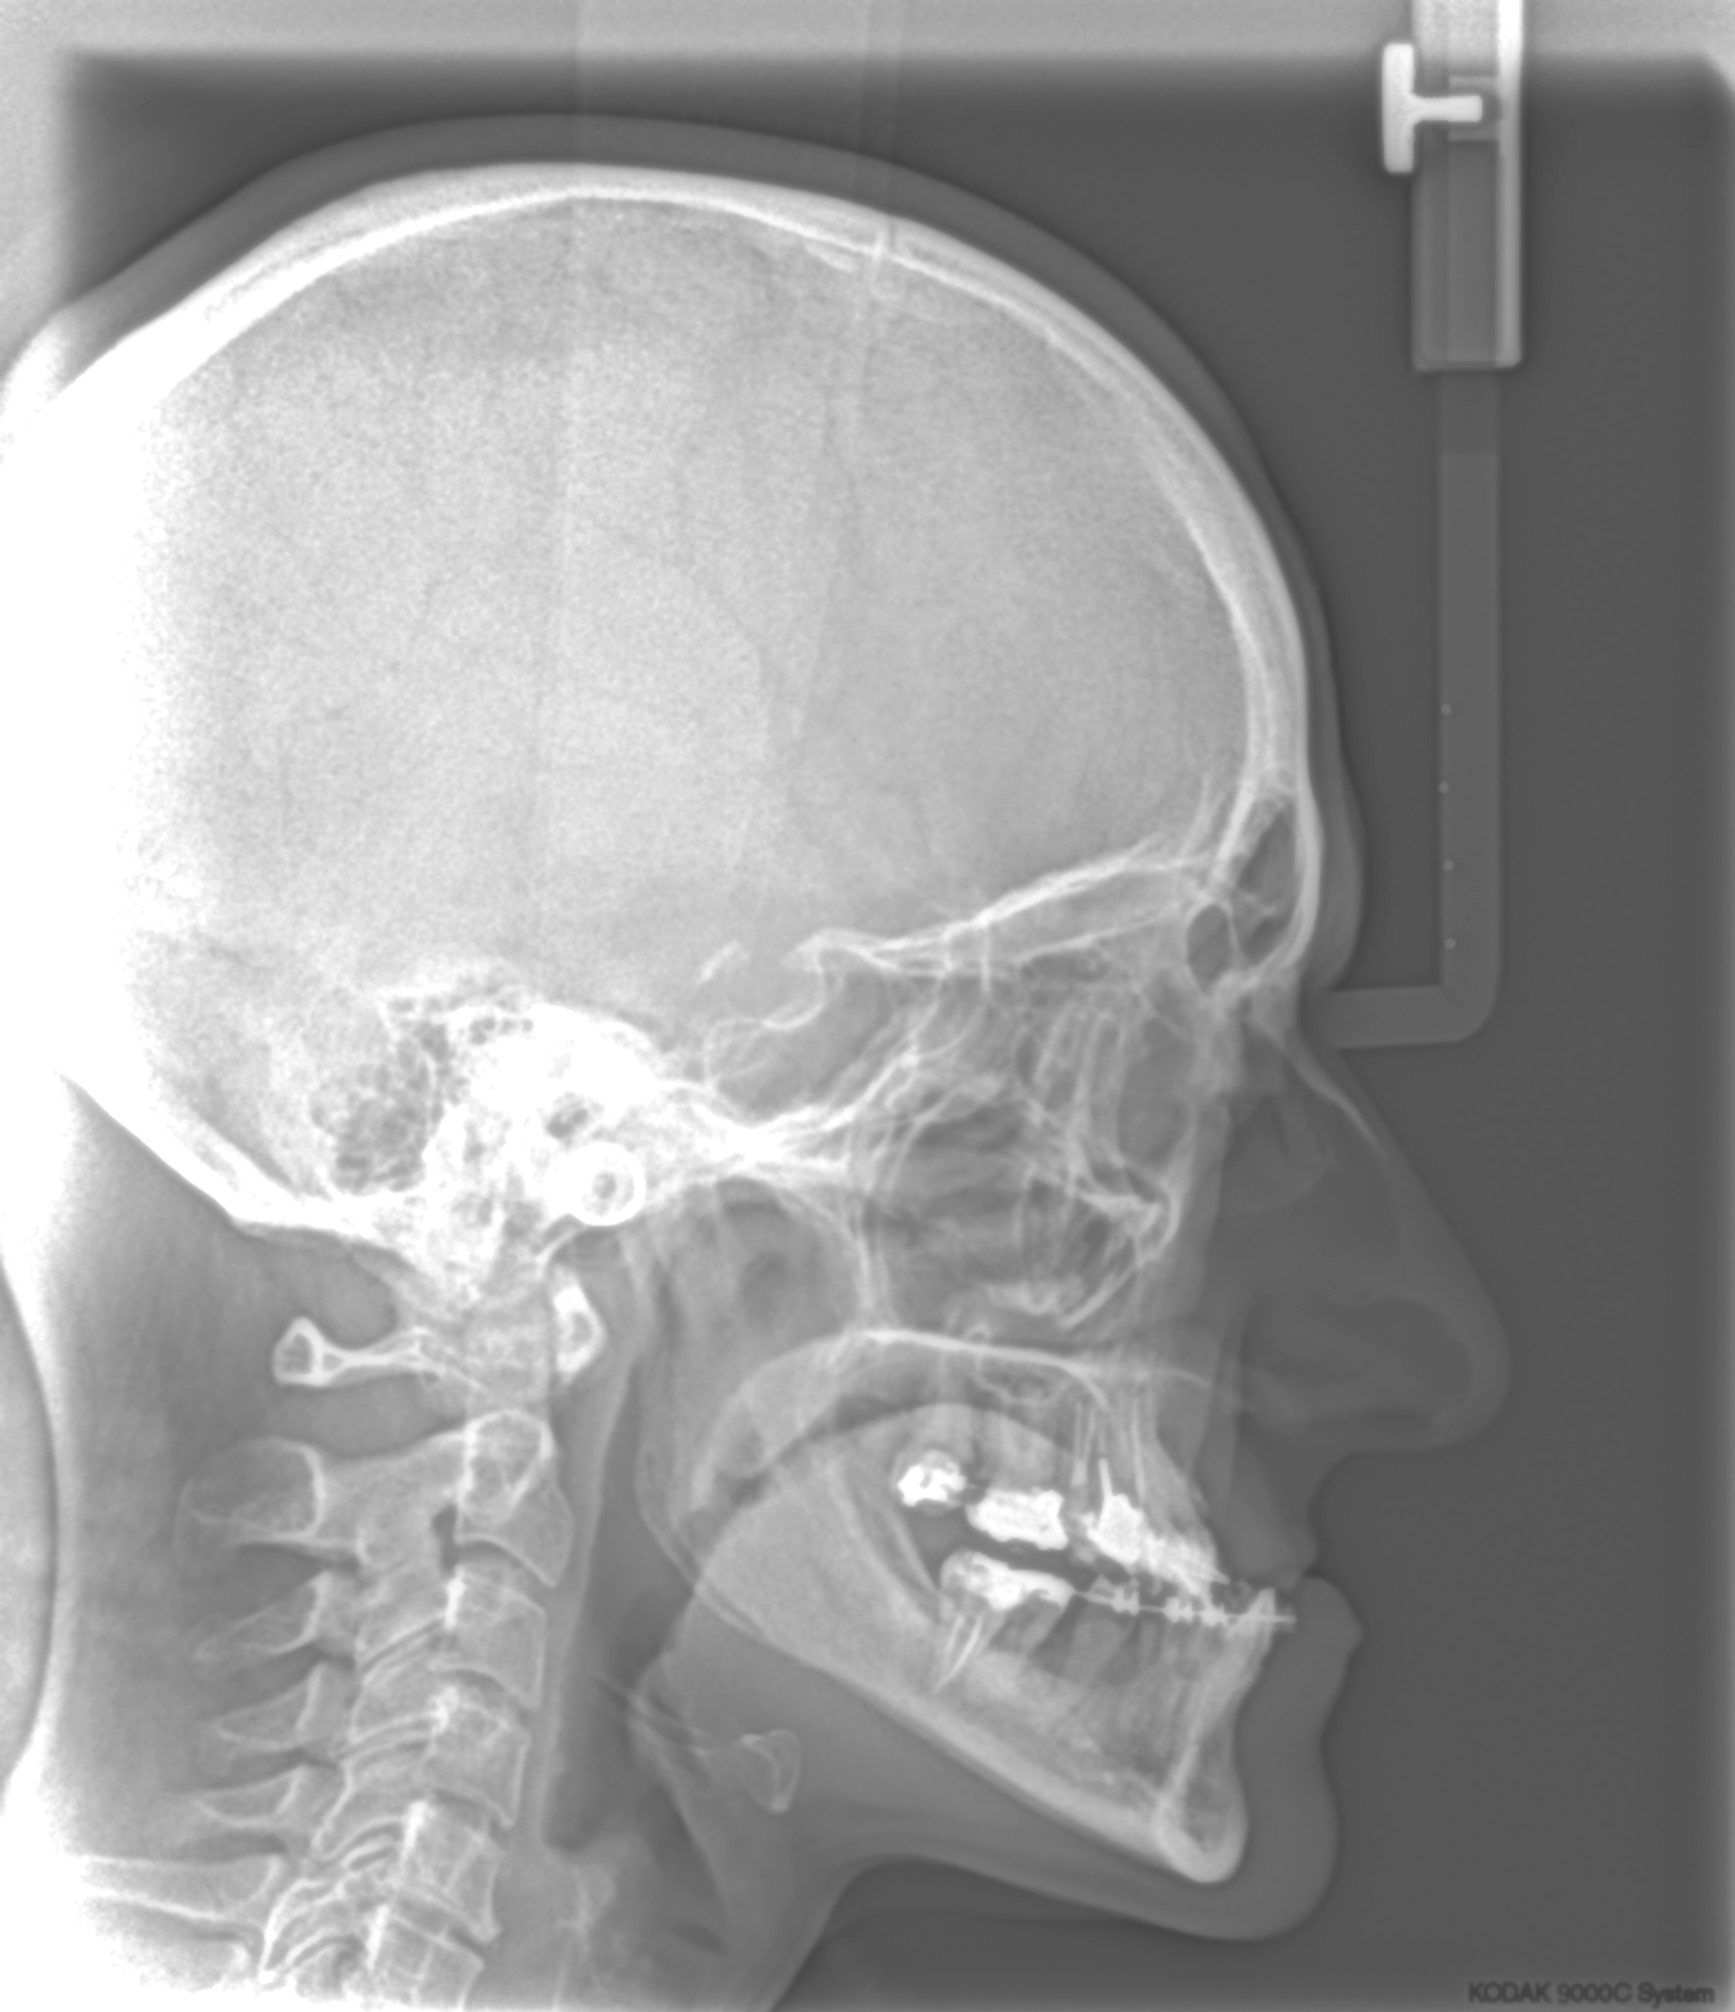

ΧΕΙΡΟΥΡΓΙΚΗ ΑΠΟΚΑΤΑΣΤΑΣΗ

Εφαρμόζεται σε ακραίες σκελετικές ανωμαλίες σε συνδυασμό πάντα με ορθοδοντική θεραπεία και σε συνεργασία με ειδικούς γναθοχειρουργούς με πολύ εντυπωσιακά και σταθερά ομολογουμένως αποτελέσματα.